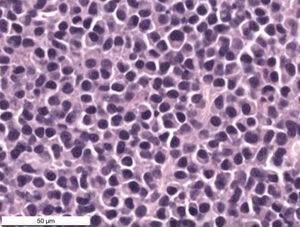

The cells had eccentric nuclei with stippled to clumped chromatin and no nucleoli. They had a moderate amount of amphophilic cytoplasm with a perinuclear clear zone. They displayed mild to moderate anisokaryosis but no mitoses were seen in ten 2.37 mm2 fields. The morphologic diagnosis from the cryostat histopathologic section was a plasma cell tumor.